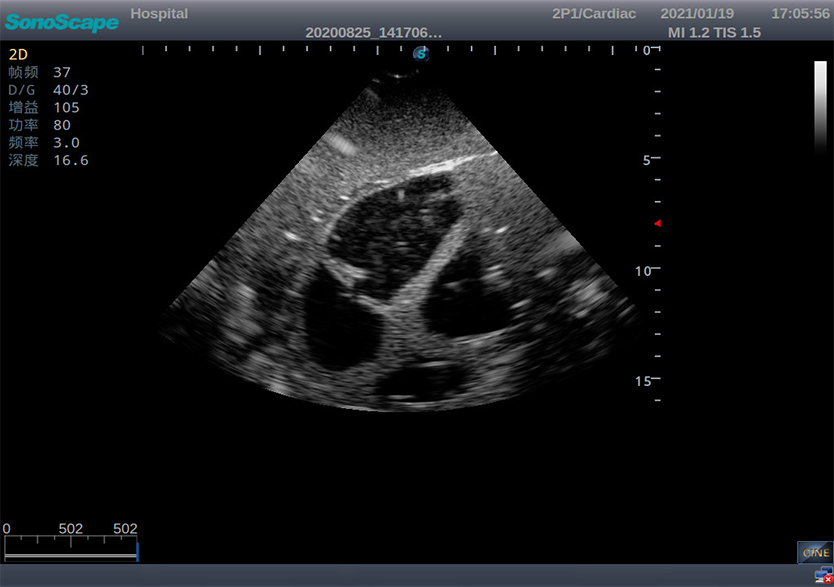

创伤超声重点评估平台2.0

产品型号 NO.TY4084

产品尺寸(mm) 987×444×269

让真实触手可及

TELLYES VIRTUALLY REAL